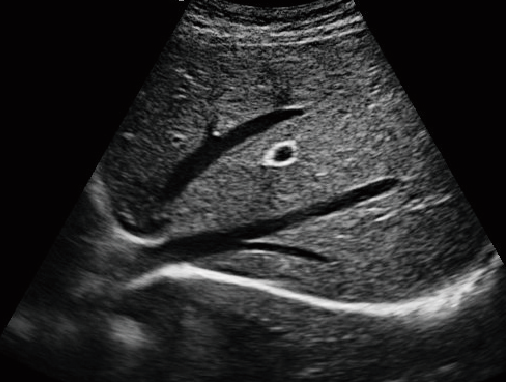

MU15便攜筆記本式獸用B超機

動物寵物超聲診斷儀

·顯示模式:B、B+B、4B、B+M、M、PW

·具有專業的動物產科軟件包,分別是狗、貓、馬、牛、羊

·適用于各種動物的臨床腹部、胸腔,心臟、肌腱、小器官、眼球、生殖系統等的檢查